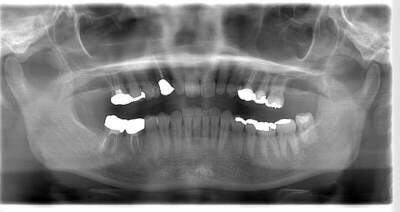

初診時のパノラマレントゲン

説明:

初診時のパノラマレントゲンです。右上の歯が虫歯によって大きく欠けているのがわかります。